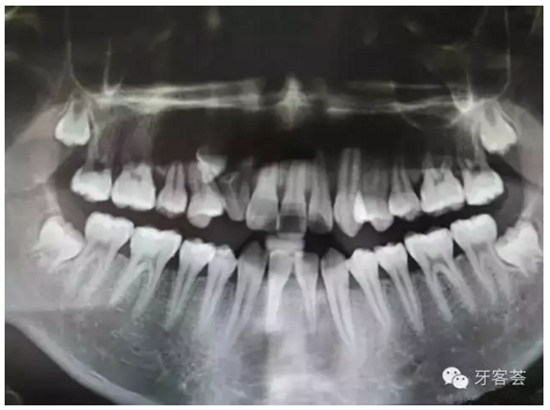

圖2:術(shù)前的全景片檢查:12牙根畸形。11、21根尖1/3橫折。可惜看不清根尖橫折。